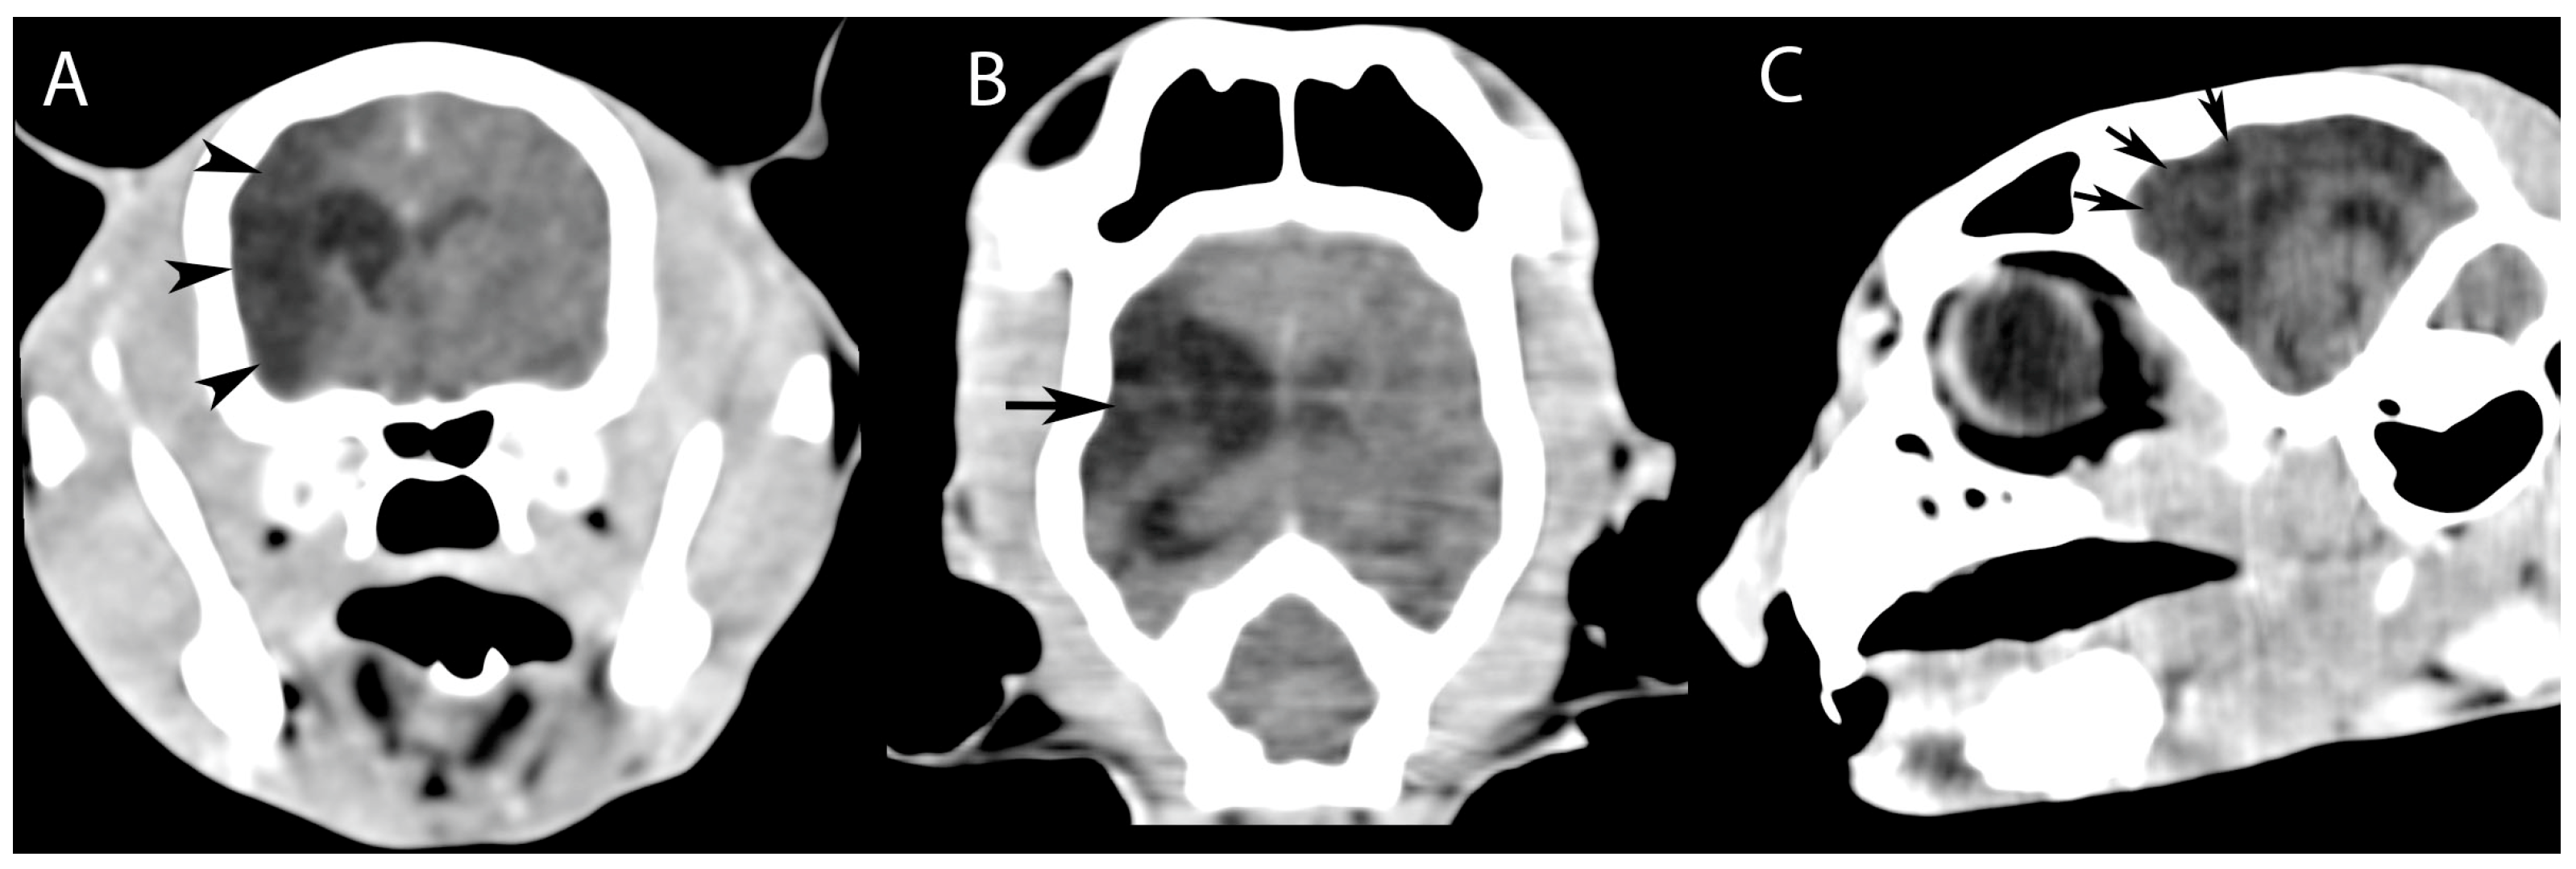

CT images of the head revealed, in addition to rhinitis, a widespread region of hypoattenuation (17 HU mean) predominantly in the right hemisphere (Figure 1), corresponding to the vascular territory of the middle cerebral artery (Figure 2). This abnormality suggested reduced blood flow in the affected brain region, leading to tissue damage and the characteristic low-attenuation appearance on the scan. The right lateral ventricle was larger than the left one.

Figure 1. Post-contrast computed tomography (CT) images of the head, obtained in transverse, coronal, and sagittal planes, demonstrate the following findings: (A) transverse view: hypodense lesions localized within the brain parenchyma in the region anatomically corresponding to the right parietal bone (black arrowheads); (B) dorsal view: hypodense lesions of the brain parenchyma involving the right frontoparietal bone region (black arrow); and (C) sagittal view: hypodense lesions of the brain parenchyma identified in the region corresponding to the frontal bone (black arrows).